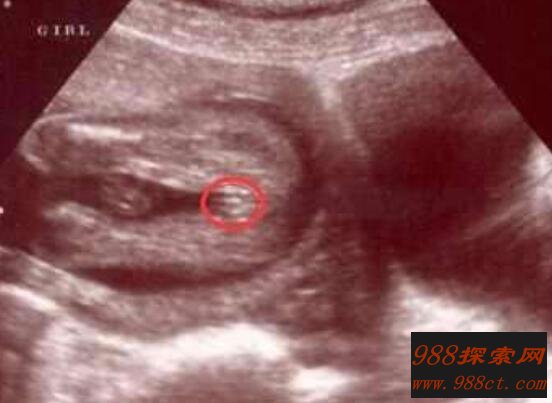

1、B超

在医院做B超是最容易看出是男孩还是女孩,它主要是通过超声波扫描,在图像上显示男孩和女孩决然不同生殖器官,不过也不排除看不清楚情况。一般来说,超声波在检测胎儿性别时候,男婴正确率要高于女婴的,当然也有一定检测误差。